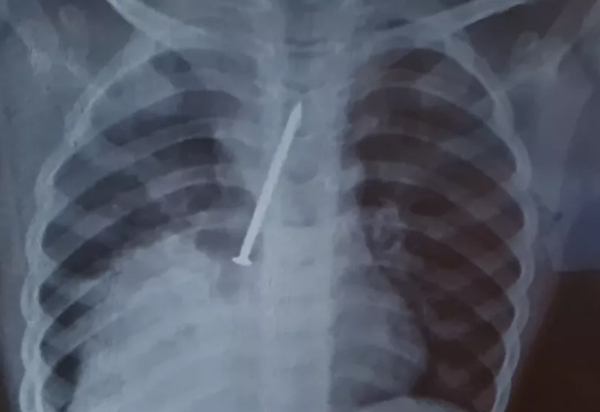

Menino morre com prego no pulmão e Polícia Civil investiga se houve negligência médica

O menino Cauan Araújo Conceição, de 3 anos, morreu por broncopneumonia, na cidade de Canavieiras, após ter os pulmões perfurados por um prego. Nesta quinta-feira (07), de acordo com informações do G1, investigações foram iniciadas para apurar se houve negligência médica nos atendimentos ao menino. A família de Cauan alega que procurou o hospital várias vezes dentro de um ano. Inicialmente, a Secretaria de Saúde do Município informou que o primeiro atendimento havia sido em 27 de junho. Depois, a pasta voltou atrás e afirmou que disse que a procura havia sido em março. A delegada Katiana Amorim esteve no hospital para checar prontuários e recolher documentos para a investigações. Ela vai ouvir testemunhas para dar seguimento ao caso.